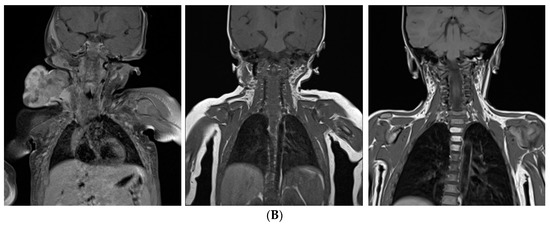

Infants and Newborns with Atypical Teratoid Rhabdoid Tumors (ATRT) and Extracranial Malignant Rhabdoid Tumors (eMRT) in the EU-RHAB Registry: A Unique and Challenging Population

by Karolina Nemes, Pascal D. Johann, Mona Steinbügl, Miriam Gruhle, Susanne Bens, Denis Kachanov, Margarita Teleshova, Peter Hauser, Thorsten Simon, Stephan Tippelt, Wolfgang Eberl, Martin Chada, Vicente Santa-Maria Lopez, Lorenz Grigull, Pablo Hernáiz-Driever, Matthias Eyrich, Jane Pears, Till Milde, Harald Reinhard, Alfred Leipold, Marianne van de Wetering, Maria João Gil-da-Costa, Georg Ebetsberger-Dachs, Kornelius Kerl, Andreas Lemmer, Heidrun Boztug, Rhoikos Furtwängler, Uwe Kordes, Christian Vokuhl, Martin Hasselblatt, Brigitte Bison, Thomas Kröncke, Patrick Melchior, Beate Timmermann, Joachim Gerss, Reiner Siebert and Michael C. Frühwaldadd Show full author list remove Hide full author list

Cancers 2022, 14(9), 2185; https://doi.org/10.3390/cancers14092185 - 27 Apr 2022

Introduction: Malignant rhabdoid tumors (MRT) predominantly affect infants and young children. Patients below six months of age represent a particularly therapeutically challenging group. Toxicity to developing organ sites limits intensity of treatment. Information on prognostic factors, genetics, toxicity of treatment and long-term outcomes [...] Read more.

Introduction: Malignant rhabdoid tumors (MRT) predominantly affect infants and young children. Patients below six months of age represent a particularly therapeutically challenging group. Toxicity to developing organ sites limits intensity of treatment. Information on prognostic factors, genetics, toxicity of treatment and long-term outcomes is sparse. Methods: Clinical, genetic, and treatment data of 100 patients (aged below 6 months at diagnosis) from 13 European countries were analyzed (2005–2020). Tumors and matching blood samples were examined for SMARCB1 mutations using FISH, MLPA and Sanger sequencing. DNA methylation subgroups (ATRT-TYR, ATRT-SHH, and ATRT-MYC) were determined using 450 k / 850 k-profiling. Results: A total of 45 patients presented with ATRT, 29 with extracranial, extrarenal (eMRT) and 9 with renal rhabdoid tumors (RTK). Seventeen patients demonstrated synchronous tumors (SYN). Metastases (M+) were present in 27% (26/97) at diagnosis. A germline mutation (GLM) was detected in 55% (47/86). DNA methylation subgrouping was available in 50% (31 / 62) with ATRT or SYN; for eMRT, methylation-based subgrouping was not performed. The 5-year overall (OS) and event free survival (EFS) rates were 23.5 ± 4.6% and 19 ± 4.1%, respectively. Male sex (11 ± 5% vs. 35.8 ± 7.4%), M+ stage (6.1 ± 5.4% vs. 36.2 ± 7.4%), presence of SYN (7.1 ± 6.9% vs. 26.6 ± 5.3%) and GLM (7.7 ± 4.2% vs. 45.7 ± 8.6%) were significant prognostic factors for 5-year OS. Molecular subgrouping and survival analyses confirm a previously described survival advantage for ATRT-TYR. In an adjusted multivariate model, clinical factors that favorably influence the prognosis were female sex, localized stage, absence of a GLM and maintenance therapy. Conclusions: In this cohort of homogenously treated infants with MRT, significant predictors of outcome were sex, M-stage, GLM and maintenance therapy. We confirm the need to stratify which patient groups benefit from multimodal treatment, and which need novel therapeutic strategies. Biomarker-driven tailored trials may be a key option. Full article